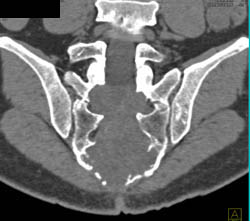

Patellar Fracture